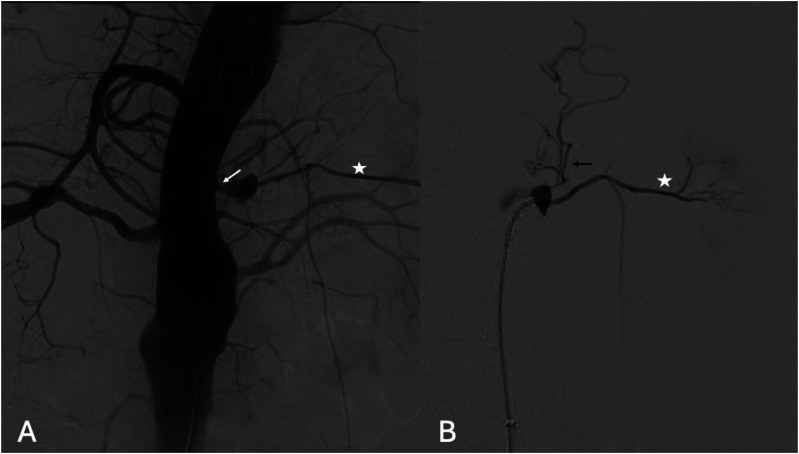

目的:描述在一名接受保守治疗的慢性 B 型主动脉夹层(cTBAD)患者中,采用偏离中心的球囊扩张覆盖支架选择性封堵远端入口撕裂(ET)的技术:一名 63 岁的男性,因慢性 B 型主动脉夹层(cTBAD)接受保守治疗,在随访时出现 FL 部分血栓形成和扩张(胸主动脉 FL 在 6 个月内从 21 mm 增至 27 mm,腹主动脉 FL 在 6 个月内从 11 mm 增至 15 mm)。未发现近端 ET。FL远端灌注是由腹主动脉中的ET造成的,ET为2毫米的肾脏附属动脉(ARA)供血。由于主动脉直径低于血管内修复的阈值,因此计划对远端 ET 和 ARA 进行选择性闭塞。对球囊扩张覆盖支架进行了改良,将覆盖支架向近端偏离中心,使其在穿过 ET 进入 ARA 后形成漏斗状闭塞。为防止术中检测到的膈动脉(PA)可能导致的FL扩张造成Ic型内漏,在改良支架和ARA的管腔内部署了线圈。出院前的计算机断层扫描血管造影显示,ARA和ET均被排除,PA出现了2型内漏:结论:球囊扩张型覆膜支架可通过偏离覆膜支架的中心形成漏斗状来进行改造,以适应不同直径的要求。

PurposeTo describe the technique of off-centering a balloon-expandable covered stent for selective occlusion of a distal entry tear (ET) in a patient, conservatively treated for chronic type B aortic dissection (cTBAD), presenting FL expansion.TechniqueA 63-year-old male, with conservatively managed cTBAD, presented at follow-up with FL partial thrombosis and expansion (thoracic aorta FL from 21 mm to 27 mm and abdominal aorta FL from 11 mm to 15 mm in 6 months). No proximal ET was identifiable. Distal FL perfusion was caused by an ET in the abdominal aorta feeding a 2 mm accessory renal artery (ARA). As the aortic diameter was below the threshold for endovascular repair, a selective occlusion of the distal ET and ARA was planned. A balloon-expandable covered stent was modified by off-centering the covered stent proximally and resulting in a funnel-shape occluder after deployment across the ET into the ARA. To prevent type Ic endoleak due to possible FL expansion caused by an intra-operatively detected phrenic artery (PA), coils were deployed into the lumen of the modified stent and the ARA. The pre-discharge computed tomography angiography showed exclusion of both the ARA and ET and a type 2 endoleak from the PA.ConclusionA balloon-expandable covered stent can be modified by off-centering the covered stent resulting in a funnel shape to adapt to different diameter requirements.